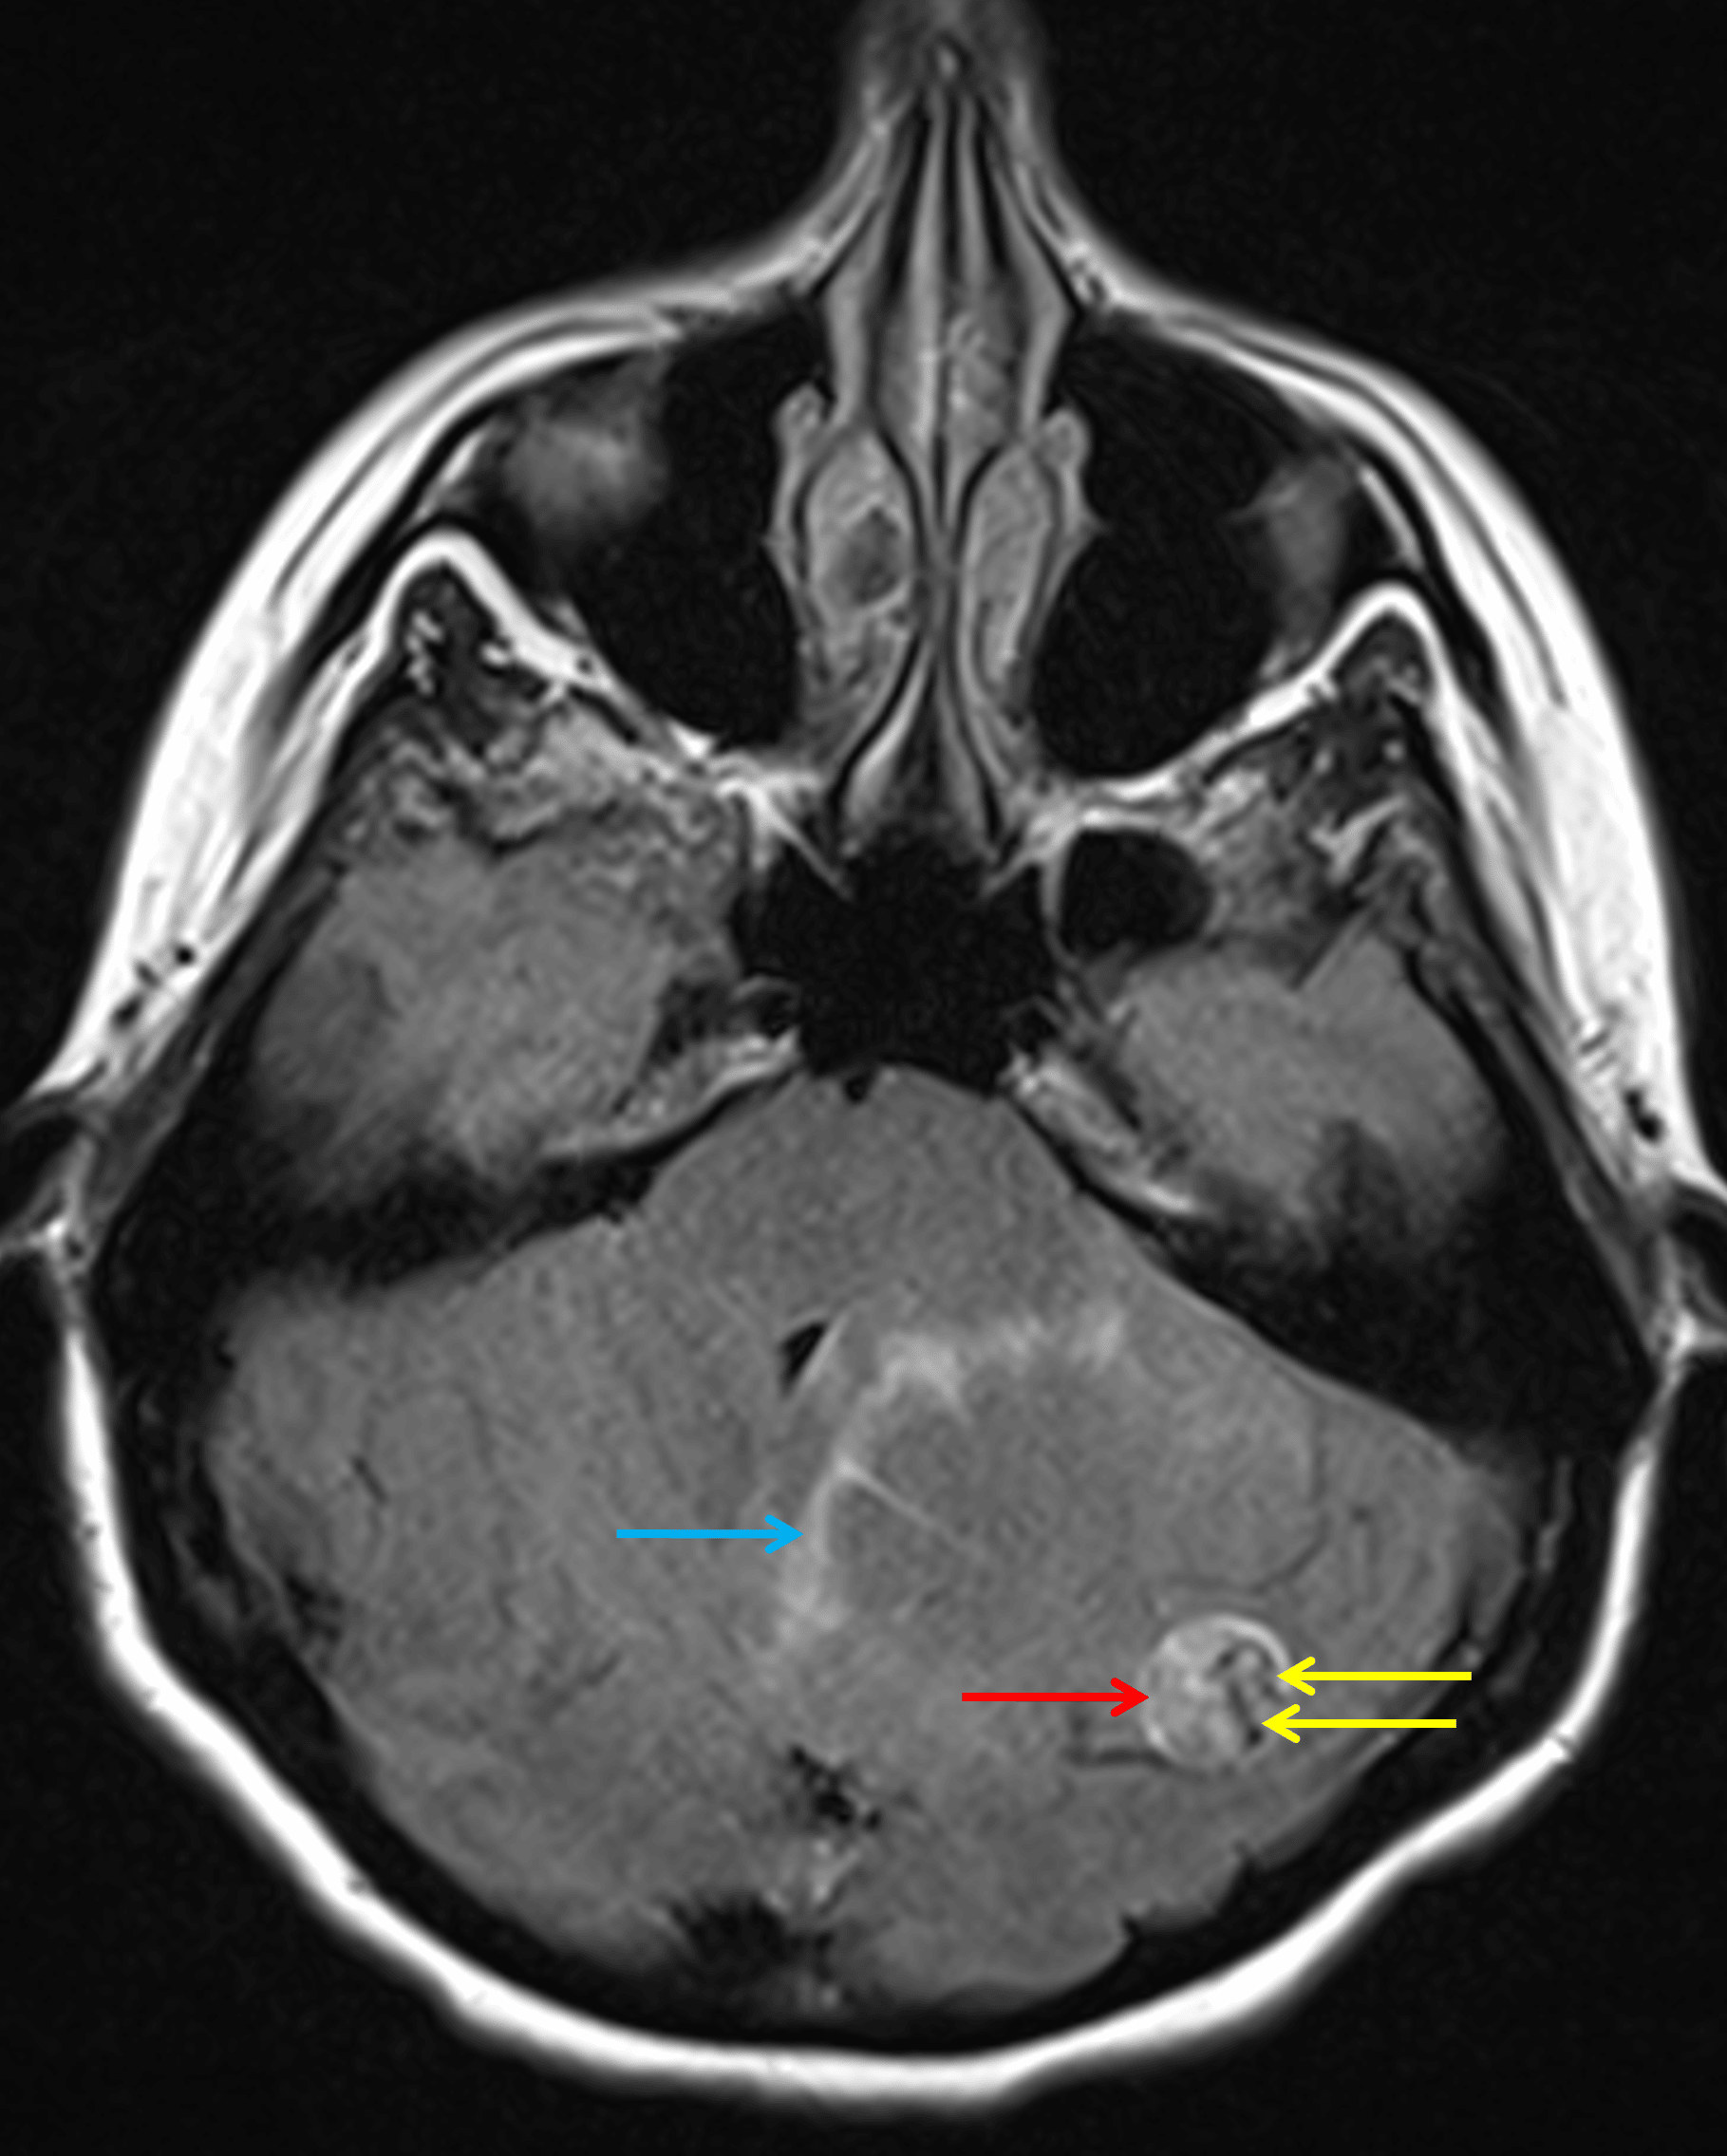

Axial FLAIR sequence demonstrates hyperintense signal within the solid component (red arrow) contrasted with serpiginous hypointense flow voids (yellow arrows). Minimal parenchymal edema is noted along the margins of the cystic component of the mass (blue arrow).